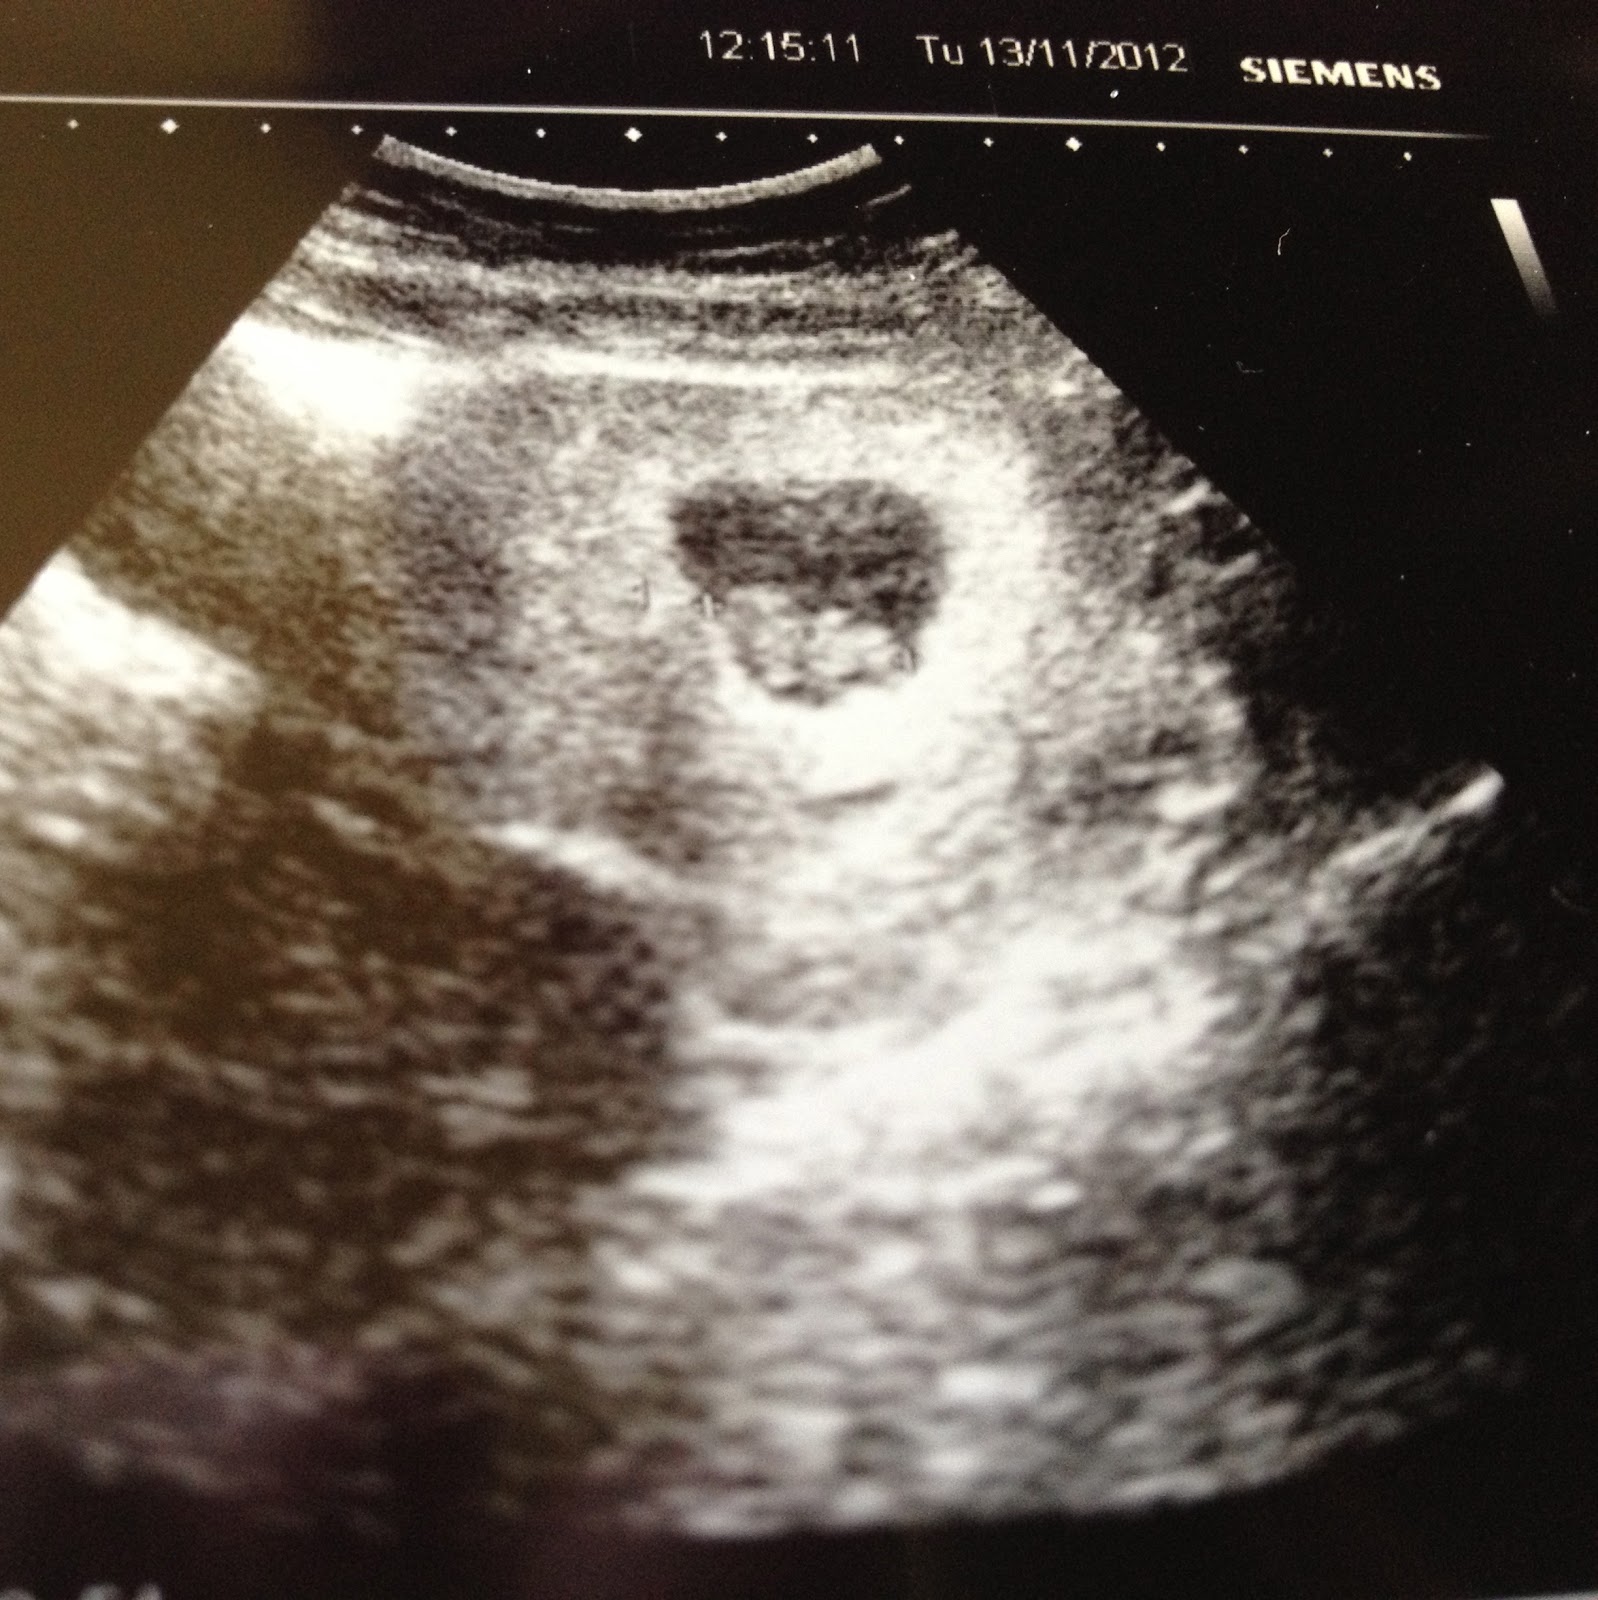

8 Week Ultrasound

13 Weeks and already sucking it’s thumb! I love this little peanut so much already!